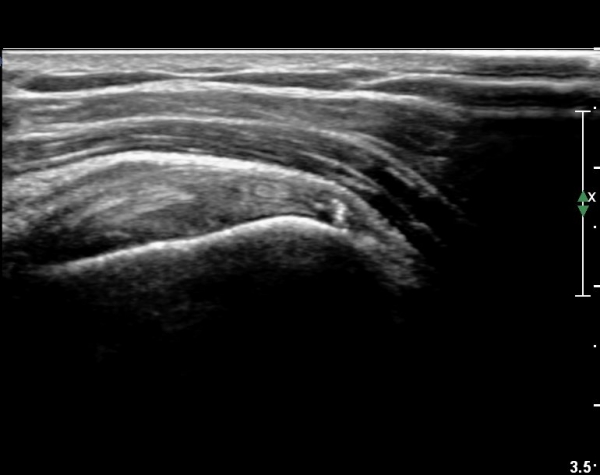

°ß°©ÇϱٰǠ Á¾´Ü¸é°Ë»ç¿¡¼­ °ÇºÎÂøºÎ¿¡ ÀÛÀº ¼®È¸È­À½¿µÀÌ °üÂûµÊ(»çÁø 2).